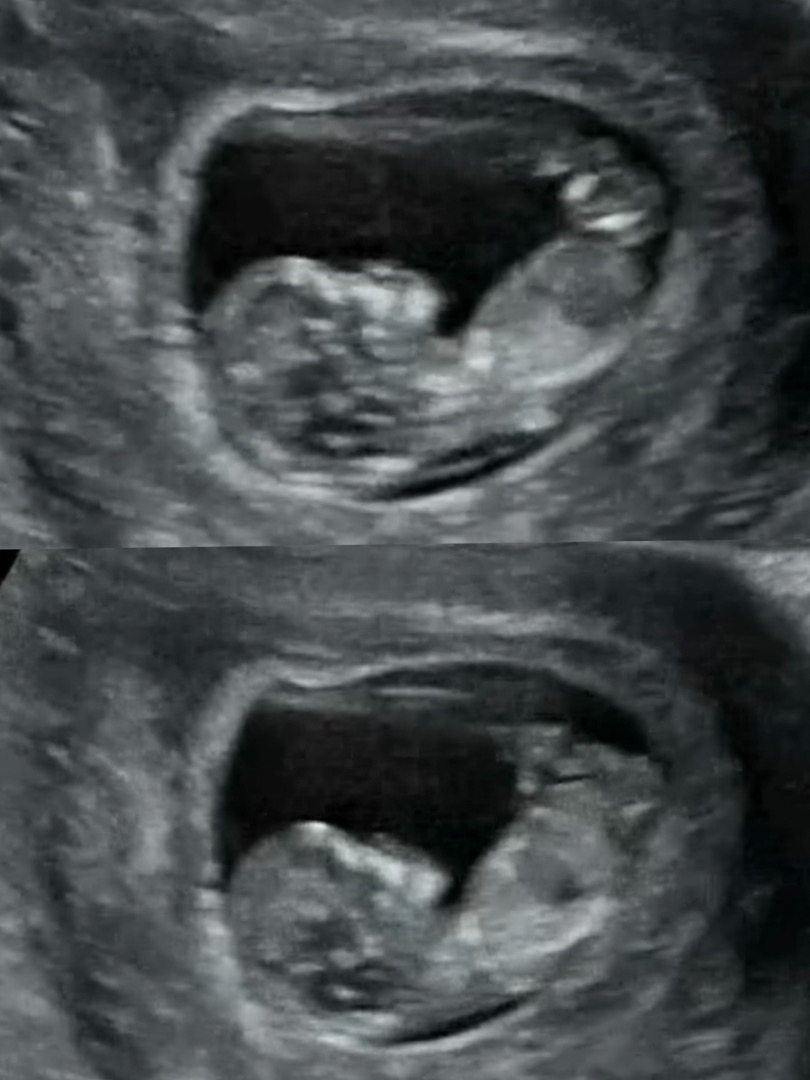

11주6일 초음파사진 성별 예측 가능할까요!?

11주6일 병원 방문하여 찍은 초음파 입니다. 건강하게만 있어다오~ 오로지 건강만을 바라는 맘이였는데, 꼬물 꽁냥 잘 지내는 모습을 보니, 기특하고 자연스레 우리아가 성별이 궁금해집니다.. 사람마음이라는게 참 간사한가봐요ㅠ_ㅠ 선생님께서는 생식기를 아직 알 수 없는 부분이라 말씀하셨는데 초음파를 볼때마다 너무 신기하고 성별이 궁금해지네요🫢 보시기에 어떠한 성별로 예측이 되시나요?😀

다리와 척추위치요 아직은 정말알수가 없어요 꼬리부분이 딸이면 안으로 들어가면서 보일꺼고 아들이면 더욱더 돌출되어서 보일꺼거든요